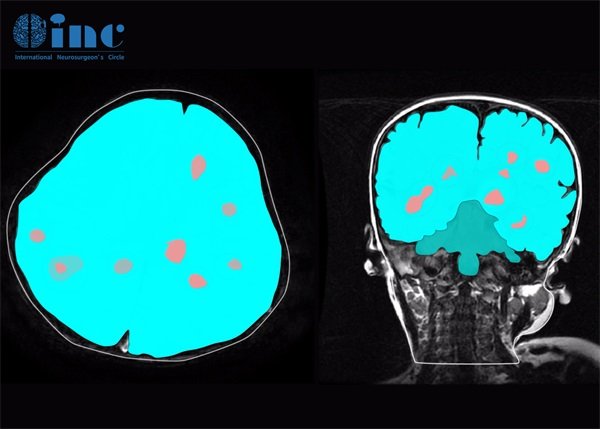

颅内海绵状血管瘤(Cavernous Angioma)是一种常见的良性血管性肿瘤,通常位于脑组织中。尽管这类病变多为良性,但由于其位置深且结构复杂,给诊断和治疗带来了不少挑战。近年来,随着磁共振成像(MRI)技术的发展,如何判断颅内海绵状血管瘤的磁敏感性,以及其在深部位置对影像学特征的影响,成为了研究的热点。

海绵状血管瘤的磁敏感性与其血管结构的独特性密切相关。这类肿瘤通常由多个血腔构成,且腔内存在高氧和低氧的血液流动。MRI可以利用这些血腔内的不同信号强度来对海绵状血管瘤进行成像,从而提高诊断的准确性。

海绵状血管瘤的特征性信号在不同的MRI序列中表现各异。例如,在T1加权序列中,其表现为低信号,而在T2加权序列中则多呈现高信号。这些特征可以帮助医生在早期阶段进行正确判断,从而做出及时的干预。

某些情况下海绵状血管瘤可能引起周围水肿,这在影像上亦会有所体现。影像学对评估血管瘤的大小、位置及其对周围组织的影响至关重要。

颅内海绵状血管瘤的深部位置意味着它们可能位于脑的深结构区域,例如基底节、颞叶等。这些位置的深度使得该病变的诊断与处理尤为复杂,在进行手术时面临更大的风险。